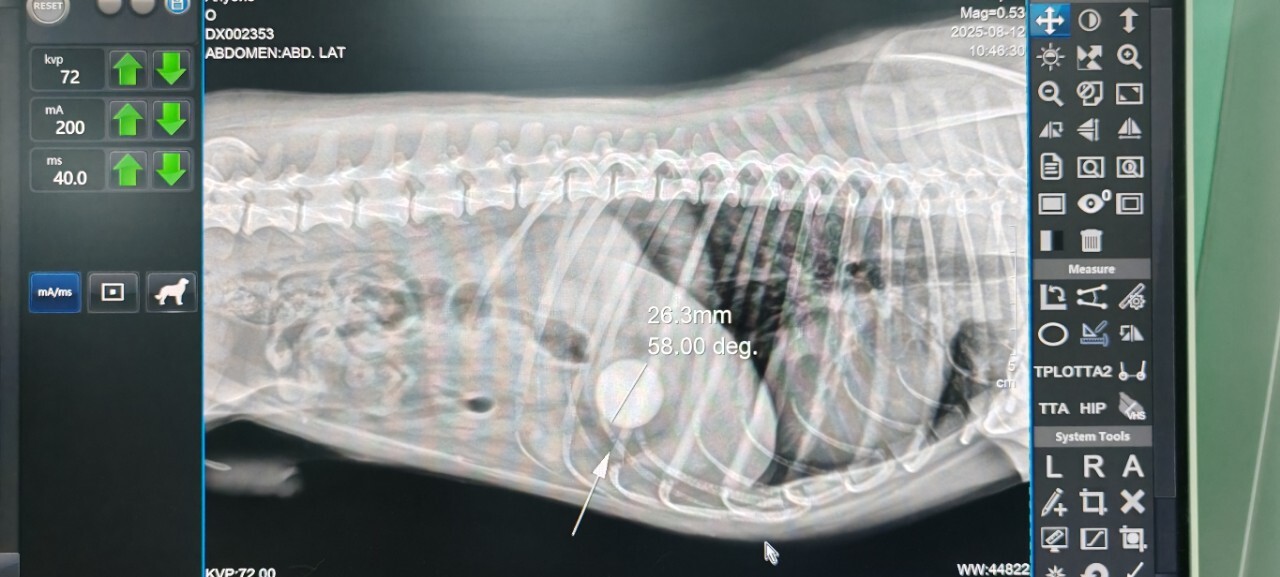

Реальный случай: ребенок играл попрыгунчиком, собака его схватила...и...проглотила.

Кончилось это операцией.

Наглядно на снимках.